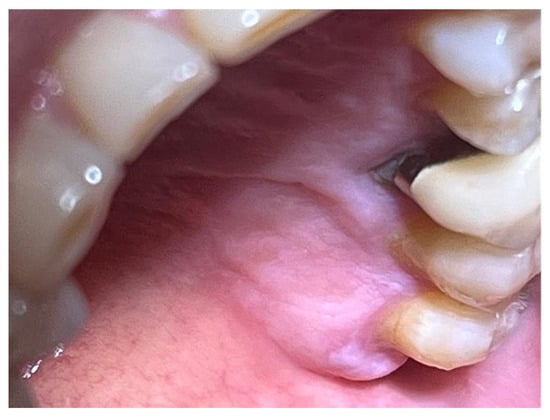

The study involved nine patients diagnosed with cardiovascular conditions, selected according to clearly defined inclusion criteria: presence of diagnosed cardiac conditions, the need for oral surgery, and signed informed consent. Exclusion criteria included patients with known allergies to the components of Glubran II, active infections, or systemic conditions contraindicating surgery. All patients were administered an antibiotic regimen consisting of Amoxicillin + Clavulanic Acid (875/125 mg), GlaxoSmithKlin, London, UK starting 24 h prior to the procedure, which was performed after obtaining cardiology clearance. Excellent results in terms of managing intra- and postoperative bleeding and tissue healing were observed in a 67-year-old patient with hypertension and diabetes mellitus, who underwent an excisional biopsy of a white lesion located on the palate with a leukoplakic appearance. The lesion, located on the palatal vault, appeared white, non-glossy, with undefined margins and soft consistency, and was non-removable via scraping biopsy (Figure 1 and Figure 2). A decision was made to surgically remove the lesion with wide incision margins to provide a biopsy sample (containing the lesion with surrounding healthy tissue) to the Department of Pathological Anatomy at the University Hospital of Rome Tor Vergata.

Figure 1. Lesion resembling leukoplakia localized on the palate, non-removable through biopsy by scraping.

Figure 2. Leukoplakia-like lesion localized on the palate following scraping with a sterile gauze.